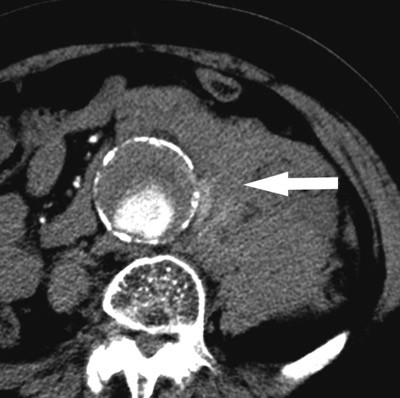

«Aneurisme» kommer fra det greske verbet «aneurynein», som betyr «å utvide». Et abdominalt aortaaneurisme er en utposning på hovedpulsåren som gir minst 50 % økt diameter (1). En mer praktisk definisjon som brukes ofte er aortadiameter > 30 mm (2). Figur 1 er en fremstilling av kartreet i abdomen med aortaaneurisme. Ruptur av aneurismet gir blødning ut i omgivende vev og medfører en livstruende tilstand hos pasienten – ubehandlet er utgangen dødelig (fig 2). Det er beregnet at om lag 1–2 % av dødsfallene i den vestlige verden skyldes rumpert aortaaneurisme (3). Tilstanden kan utvikle seg i hele aorta, men er hyppigst forekommende i infrarenale abdominalaorta. Data i denne artikkelen vil derfor vesentlig omhandle abdominalaorta med eller uten involvering av iliakalkar.

Når abdominale aortaaneurismer gir symptomer, er det som oftest pga. ruptur eller akutt ekspansjon, såkalt truende ruptur. Pasienter med ruptur får ofte akutte smerter i abdomen med ev. utstråling bak i rygg/flanke eller hofte/lyske. Ofte er rumperte aortaaneurismer palpable og ømme hvis ikke pasienten er for adipøs. I ca. 20 % av tilfellene skjer rupturen fortil, og pasientene forblør før de rekker å komme til sykehus. Hos de resterende 80 % skjer rupturen med blødning retroperitonealt, noe som gir et begrenset hematom og øker sjansen for overlevelse.